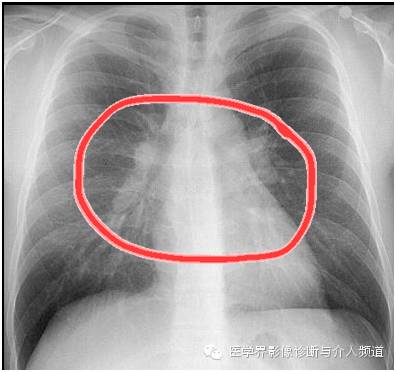

对比一张正常胸片:

看出异常所在了吗?

异常:双肺门淋巴结肿大。

到这里一张胸片中观察到的异常就结束了,再结合非常重要的临床病史,你得想到这个病–结节病,本病例为急性结节病。